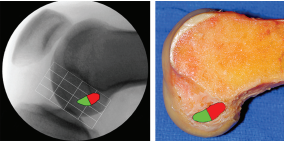

方法:221名医生在一具膝关节标本和一张有刻度的膝关节侧位X线片上表明了他们预期建立的股骨隧道的位置。然后每个外科医生在关节镜下手术演示定位股骨隧道的位置。这个位置是用术中C臂透视获取的。以股骨外侧髁的网格为参照,比较了预期建立和实际获得的隧道位置之间的欧几里德距离(两点之间的直线距离)。根据外科医生的观察入路(前内侧[AM]或前外侧[AL])、隧道定位策略(偏心定位器、解剖标志估计、ACL尺或C臂透视)和规定的钻孔技术(经胫骨钻股骨隧道、前内入路钻孔或由外向内钻孔)对数据进行分析。

结果:通过AM入路观测髁间窝外侧壁的医生(平均偏差距离9.5)相对于比通过AL入路的医生(平均偏差距离15.1)实际获得的隧道位置离预期建立的股骨隧道位置更近(P<0.0001)。使用偏心定位器定位股骨隧道(平均偏差距离14.5)和解剖标志估计定位股骨隧道位置(平均偏差距离12.9)的医生与使用ACL尺定位隧道(平均偏差距离8.1)和术中C臂透视定位的医生(平均偏差距离4.3)相比,实际得到的隧道位置与预期建立的隧道位置之间的平均偏差距离之间有显著性差异(P<0 .0001)。医生选择的钻孔技术(AM入路,经胫骨钻股骨隧道,或由外向内钻孔)对预期建立隧道的位置和实际获得的位置之间的距离偏差没有影响。然而,使用经胫骨钻孔获得的髁间窝切迹的股骨隧道的平均位置更高(P<0 .042)。

结论:与用AL入路观察的医生相比,通过AM入路观察的医生实际得到的股骨隧道位置更接近于预期建立的隧道位置。使用术中C臂透视法定位股骨隧道位置的医生最接近他们的预期建立的隧道位置。那些使用解剖标志估计或偏心定位器的医生实际获得的隧道位置和预期的隧道位置之间的距离最大。